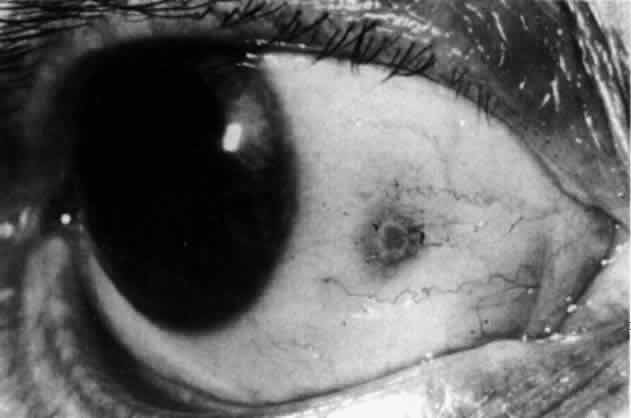

In contrast to simple episcleritis, the infiltration and edema of nodular episcleritis are localized to one part of the globe, forming a nodule and some surrounding congestion (Color Plate 1B). The nodule can be moved over the underlying sclera, which is not edematous. The scleral plexus of vessels can be distinguished deep to the nodule, lying flat on the sclera and slightly congested but otherwise normal in color and configuration (Figs. 15 and 16). Episcleral nodules may be single or multiple but do not undergo necrosis (see Fig. 16). After multiple attacks of nodular episcleritis in the same location, the superficial lamellae of the sclera show some alteration and become slightly more transparent in this one area.

Fig. 15. Episcleritis. In episcleritis, the vascular networks of the conjunctiva, episclera, and sclera are all congested. The edema is confined to the episcleral tissue so that the reflected light from the sclera shows no displacement. (Watson PG, Hayreh S, Awdry P: Episcleritis and scleritis. Br J Ophthalmol 52(3):278–279, 1968)

Fig. 16. Deep vessels, which are normal in configuration, can be traced beneath edematous nodules lying flat on the sclera. (Watson PG: Connective tissue disorders and the eye. In: Recent Advances in Ophthalmology, Vol 5, pp 214–277. London, Churchill-Livingstone, 1975)